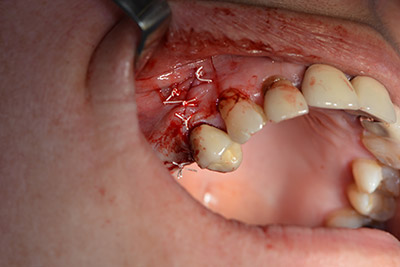

Обработка на носната лигавица

Снимка 13

Наклонено пробиване с дрил

Снимка 14

Имплантът е поставен и костта е изградена. В този случай, поради големината на зоната за аугментация, автогенните костни парченца, събрани с костен сондаж след имплантирането в зона 16 и фенестрацията в зона 14, са смесени с костозаместващ материал.

Използвана е абсорбираща мембрана като бариера на букалната страна и покритие на аугментацията. Накрая са поставени устойчиви на слюнка конци (Фиг. 15 до 19).

Аугментация с автогенна кост

Снимка 15

Снимка 16

Имплантиране

Снимка 17

Снимка 18

Закриване на ламбото с устойчиви на слюнка конци

Снимка 19